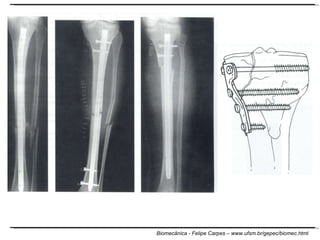

E quando a resistência não é suficiente? Fratura Hematoma (vasos rompidos) Fluxo sanguíneo interrompido Formação de um calo mole Preenchimento a parte fraturada Osteoclastos digerem as estruturas mortas Forma o calo ósseo (dá estabilidade) Atividade dos osteoblastos Consolidação do osso novamente Ação dos osteoclastos para reduzir o calo ósseo que ficou

E quando a resistência não é suficiente?